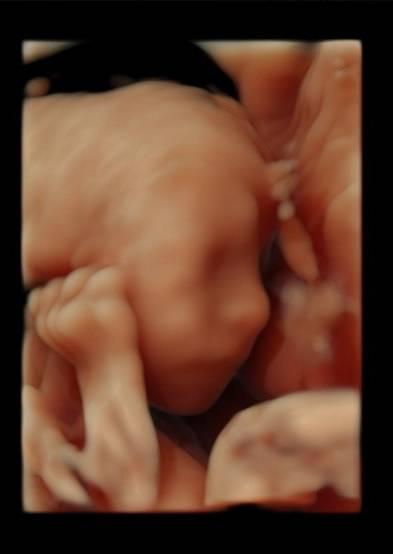

Guten Abend an euch Mitkugelnden Wir waren heute bei der Feindiagnostik und es ist alles bestens!! Die Dame hat uns ihre Kaffeebohne schön hingehalten, damit man super sehen konnte, das Sie ein Mädchen wird Wir freuen uns riesig! Laut Messung hat Sie ca. 500g und ist 27cm lang. Hach ja, Liebe Liebe Liebe

Bild zu Feindiagnostik mit eindeutigem Outing 😍 - Forum für Januar - Mamis